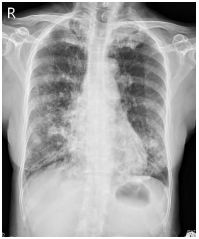

8.右胸痛 3 個月